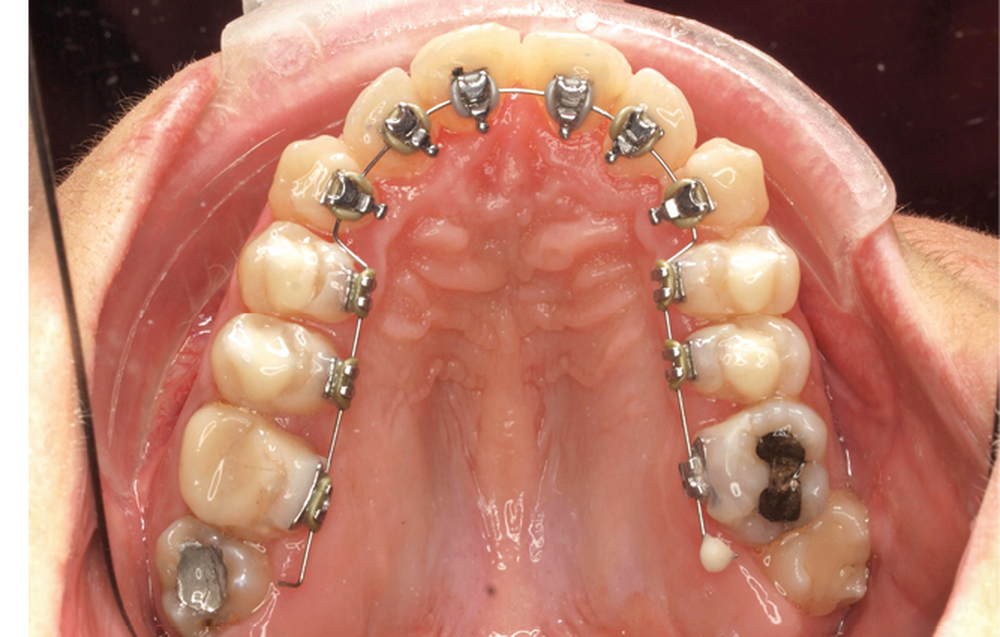

Le traitement est effectué avec un appareil lingual bimaxillaire et des attaches en .018 x .025 à insertion horizontale. L’appareil est réalisé intégralement au cabinet à partir d’un set-up conçu selon les objectifs décrits.

- Premier rendez-vous (fig. 2a) : l’arcade maxillaire est appareillée et un arc NiTi .014 en expansion est placé. L’arcade mandibulaire reçoit des cales rétro-incisives pour lever l’occlusion inversée. Par confort, des cales prémolaires, sans contact avec les dents antagonistes, sont posées pour réduire l’inocclusion latérale.

- Deuxième rendez-vous (fig. 2b) : les dents restantes sont collées et le même arc NiTi .014 est maintenu. Les cales rétro-incisives sont déposées et l’arcade mandibulaire est collée, un arc NiTi 0.014 posé.

- Troisième rendez-vous (fig. 2c) : les arcs NiTi .014 sont religaturés pour améliorer le nivellement-alignement.

- Quatrième rendez-vous (fig. 2d) : des arcs TMA .017 x .017 sont posés. Les premières et deuxièmes molaires sont collées en vestibulaire avec un arc sectionnel NiTi 0,019×0,025.

- Cinquième rendez-vous (fig. 2e) : des arcs TMA .017 x .025 sont posés et des tubes linguaux collés sur 17 et 27 pour le port d’élastiques criss-cross nocturnes.

- Sixième rendez-vous (fig. 2f) : les cales sont déposées. Un pliage de finition sur 21 est réalisé pour améliorer son angulation.

- Septième rendez-vous : les appareils sont déposés. Une empreinte numérique est prise pour réaliser trois aligneurs afin de parfaire le résultat occlusal et esthétique (fig. 3a-h).